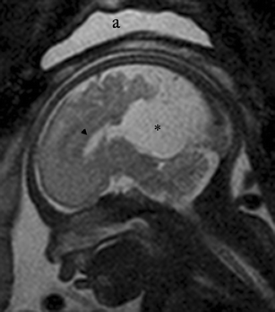

Aicardi syndrome is an X-linked dominant disorder characterized by the pathognonomic association of three clinical signs: agenesis of the corpus callosum, infantile spasms, and chorioretinal lacunae. This is a severe syndrome with an estimated survival rate of 76% at 6 years and 40% at 14 years and a maximum developmental level like a 12-month-old baby in 91% of cases. We illustrate a case of Aicardi syndrome with bilateral, small chorioretinal lacunae, infantile spasms with a typical hypsarrhythmia, defects of thoracic vertebra and bilateral absence of the12th rib associated with an arachnoid cyst of the quadrigeminal cistern, and presence of the corpus callosum with a favorable outcome.

Fig. 1